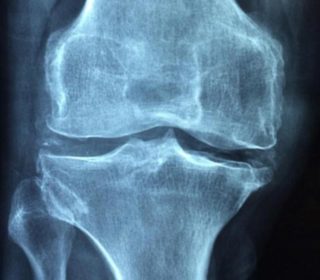

Již jsme přinesli výsledky několika metaanalýz, které potvrdily účinnost a bezpečnost aplikace kmenových buněk v léčbě osteoartritidy, tj. chronického onemocnění kolenního kloubu spojeného s destrukcí